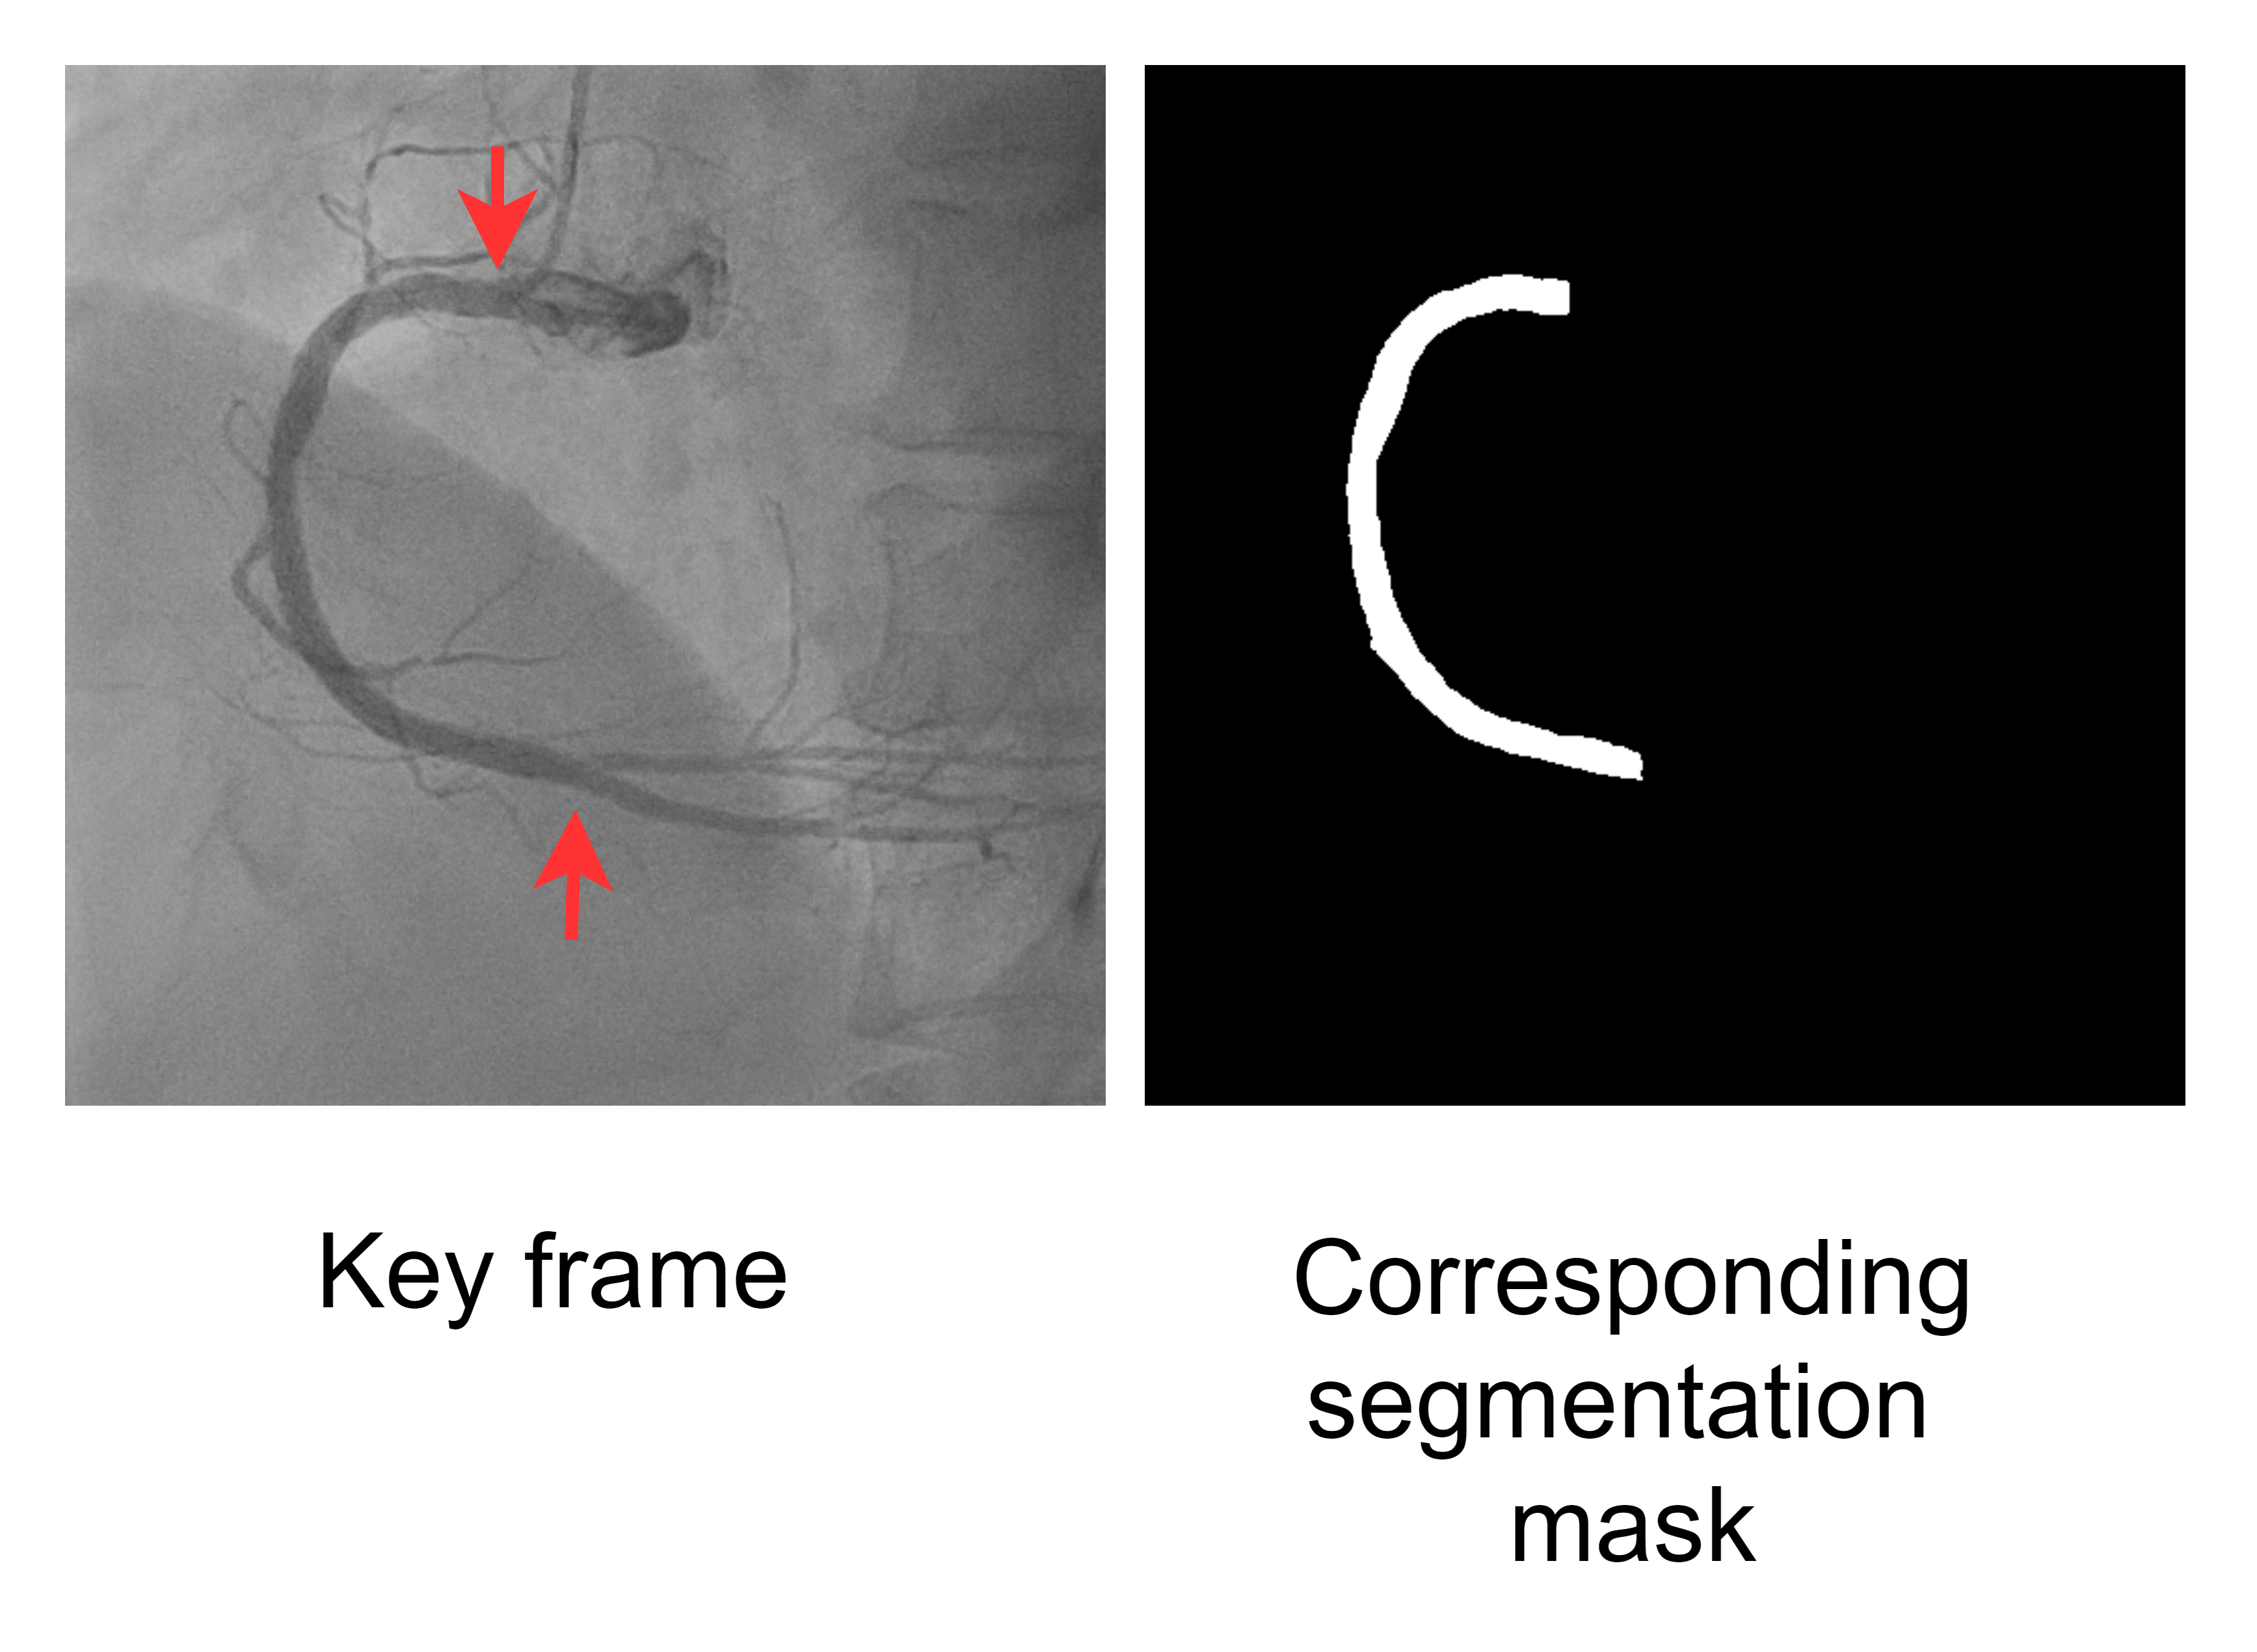

Figure 1: Schematics of methodology. (A) Workflow of the proposed angiography analysis pipeline with three main stages: extraction of key frames from video, vessel segmentation of the selected frames, and stenosis measurement through calculating vessel width, giving stenosis location and severity. (B) Key frame extraction process, showing machine prediction scores, left: two frames from the same video, one non-key (score: 0.000) and one key (score: 0.922), right: a top-5 key frame. (C) Illustration of labeled frames. (a) key frame. (b) vessel not fully formed. (c) contrast agent starts fading. (d) vessel has shifted out. (D) A key frame with corresponding segmentation label (the vessel region between the red arrows is the desired segment for segmentation). (E) Proposed stenosis measurement algorithm. Vessel width along the centerline is plotted to locate the minimum. Note that orange arrow in (c) points to the position of the most severe stenosis.

After obtaining high-quality key frames, we applied vessel segmentation on them in order to extract clear vessel shapes out of the possibly noisy backgrounds. For vessel segmentation, we implemented a U-Net model [29]. U-Net [11] is widely used in biomedical image segmentation due to its capability to preserve both global structure and local details; its shortcut connections between contracting and expanding paths facilitate feature reconstruction. Our model consisted of 5 convolutional blocks, followed by a symmetric set of 5 up-convolution blocks. Shortcuts by concatenation were introduced between each convolutional block and its corresponding up-convolution block with the same number of channels. The network took a 512x512 pixel image as input and produced a 512x512 pixel segmentation mask. The U-Net segmented the main part of the vessel i.e. the segment between the catheter-vessel junction and the bifurcation point of the RCA (Fig. 1D).